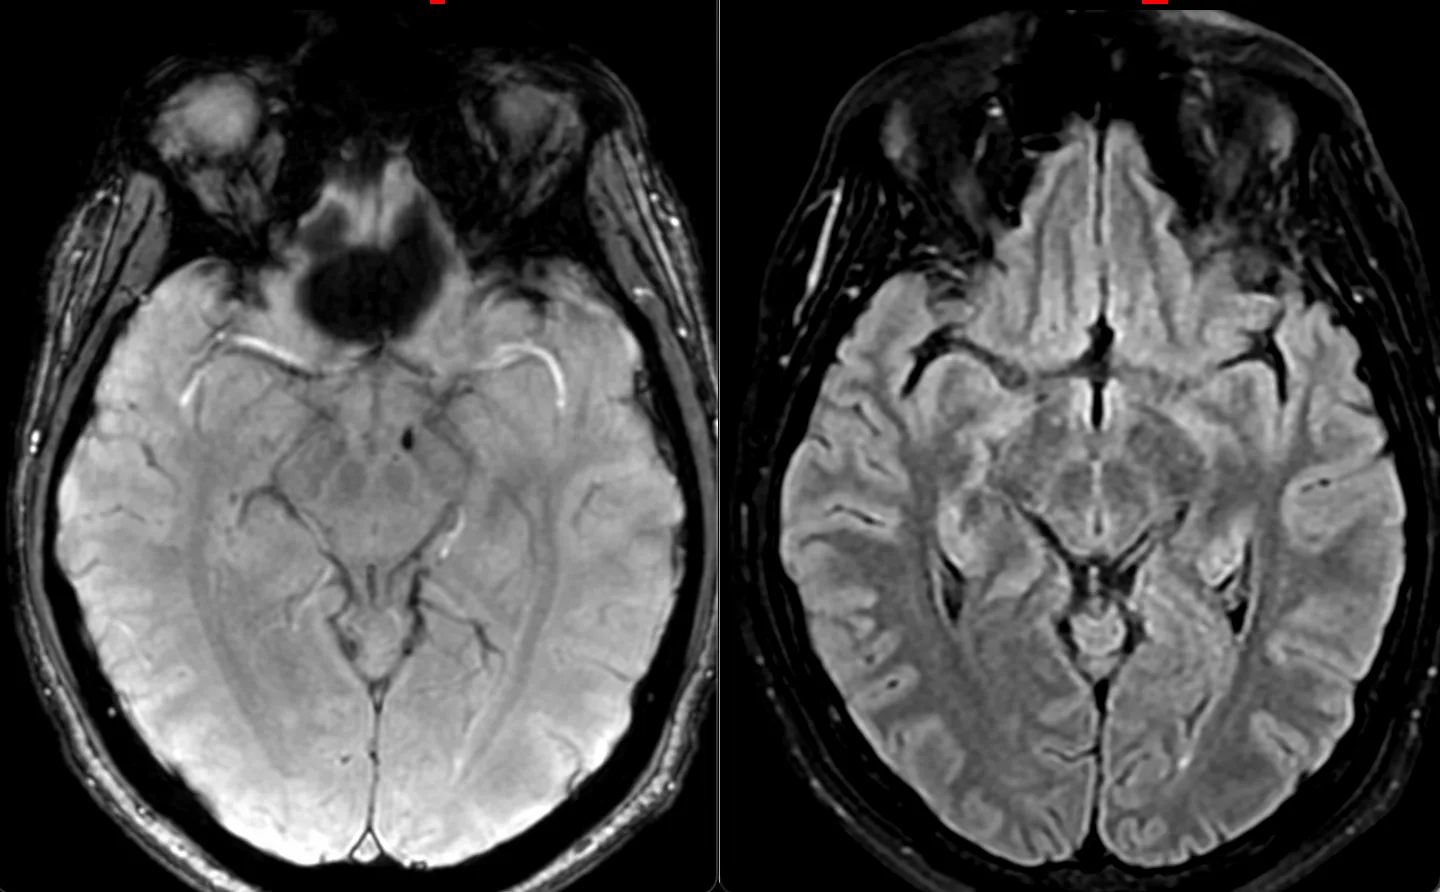

Мужчина 35 лет, месяц назад упал с высоты двух метров, сейчас не полностью ориентирован в месте и времени. Типичная (кроме мозжечка справа) картина травматического аксонального повреждения 3 степени (с поражением ствола). Множественные мелкие точечные и линейные микрокровоизлияния, вокруг части из них видны глиоз/отек. А вот в мозжечке, реально, нечасто такое увидишь. Но бывает. Типа, как вот здесь: